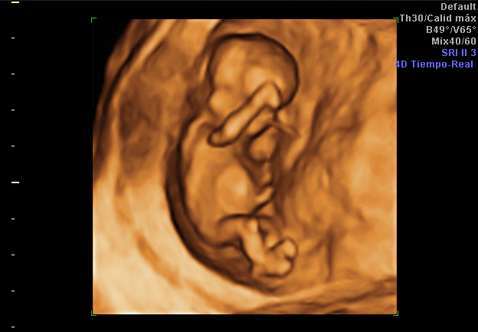

Ultrasonido 3D

Obtén imágenes detalladas y realistas de tu bebé con la última tecnología en ultrasonido.